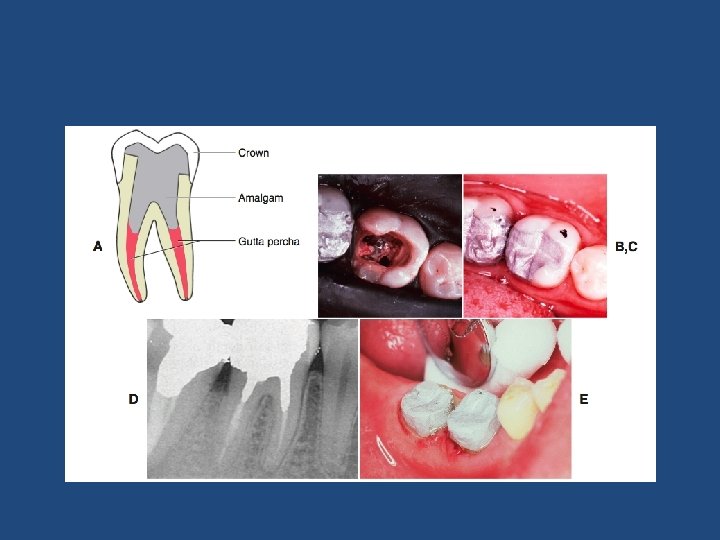

Endodontik Tedavili Dişler • • • Amalgam veya Kompozit. Dolgu Dentin Pini, Oluk veya Yuva Uygulamaları Prefabrike Metal Kanal Çivisi Fiber Post Döküm Post-Core CAD-CAM ile Üretilmiş Postlar

• Post ile en uygun yük dağılımını ve en fazla tutuculuğu sağlamak için postun uzunluğunun en az ya üstüne hazırlanacak kron yüksekliği kadar olması, ya da kökün uzunluğunun 2/3’ünü kaplaması gerekmektedir. • Apikal sızıntıyı önlemek için de kök ucunda en az 4 mm kadar gütta perka bırakılmalıdır. • Bilezik (Ferrule) etkisi